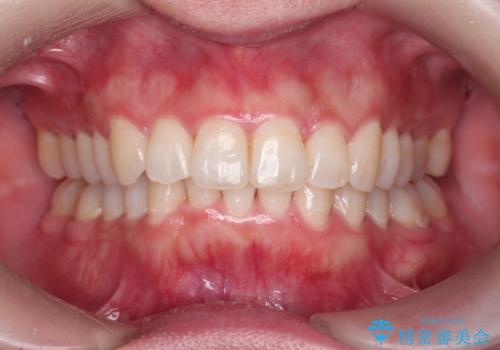

前歯をさげたい 歯を抜かずに マウスピース矯正で治したい

[ インビザライン矯正 ]マイクロインプラント用いた大きな遠心移動

担当医 大元洋佑